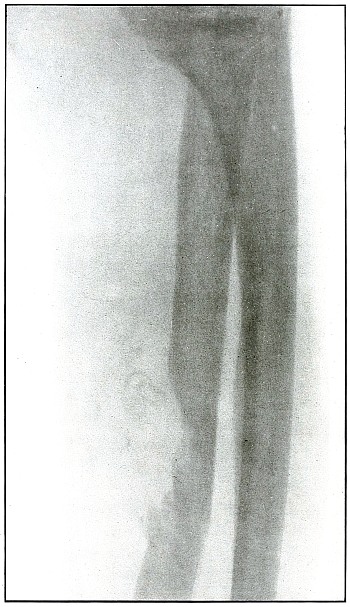

| 25. |

Gunshot fracture, radius |

60 |

| 26. |

Gunshot fracture, radius |

62 |

| 27. |

Gunshot fracture, radius |

64 |

| 28. |

Gunshot fracture, radius |

66 |